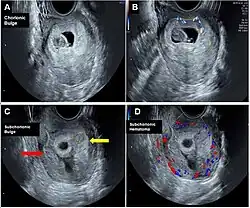

Other nameschorionic bulge

Chorionic bump is a rare medical condition defined as an irregular, convex bulge or protrusion from the choriodecidual surface into the gestational sac.[1][2] It is medically defined as a separate entity from a chorionic hematoma.[3]